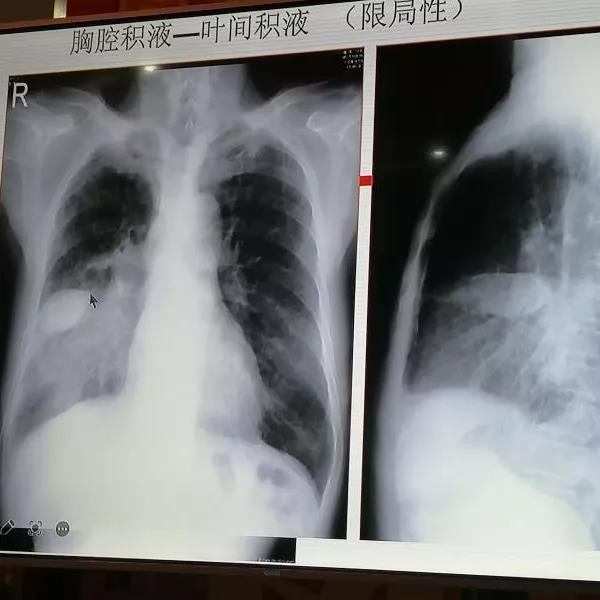

常见X线片判读并进行现场判读骨折、肠梗阻、股骨头坏死等异常X线片

现场读片